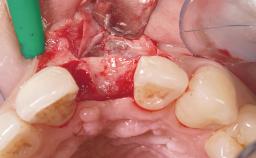

Early Placement of an Implant in a Maxillary Right Central Incisor Site

This 41-year-old female patient was referred to the clinic for the replacement of the right central incisor, since the tooth had developed a root fracture in the long axis that made extraction necessary. The healthy, non-smoking patient was first seen with the tooth still in place. A detailed Esthetic Risk Assessment was performed.The patient was worried about her dental esthetics and had high expectations for a successful treatment outcome from an esthetic point of view. The patient had a medium lip line that displayed parts of the gingiva in the anterior maxilla upon smile.

Bone Augmentation Horizontal|Simultaneous

Augmentation Materials Autogenous chips|Xenogenous|Membrane